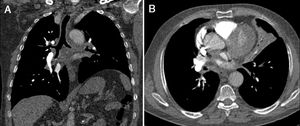

A 60-year-old male presented with complaints of chronic cough, occasional mucus secretion, and dyspnea. Coronal CT scans revealed diffuse thickened tracheobronchial wall (Fig. 1A). Axial CT scan showed atelectasi in the lingular segment of the left upper lobe (Fig. 1B). Three-dimensional volume-rendered air-specific coronal plan MDCT image (Fig. 2A) and virtual CT bronchoscopy (Fig. 2B) demonstrated obstruction of the left main bronchus. Bronchoscopic biopsy diagnosed diffuse tracheobronchial amyloidosis.

Fig. 2.

Three-dimensional volume-rendered air-specific coronal plan MDCT image (A) and virtual CT bronchoscopy (B) demonstrate obstruction (frame and arrow) of the left main bronchus.